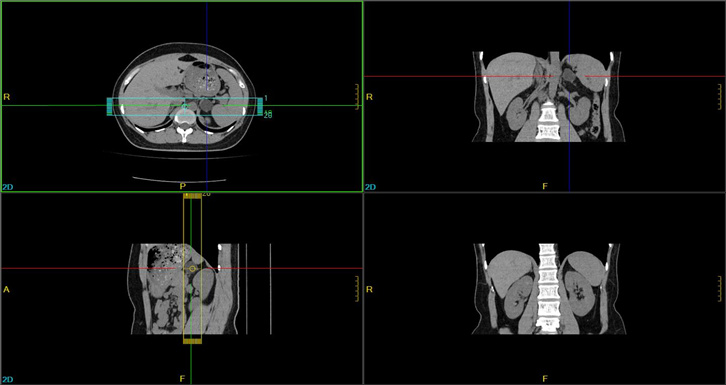

腹部CTA三维重建